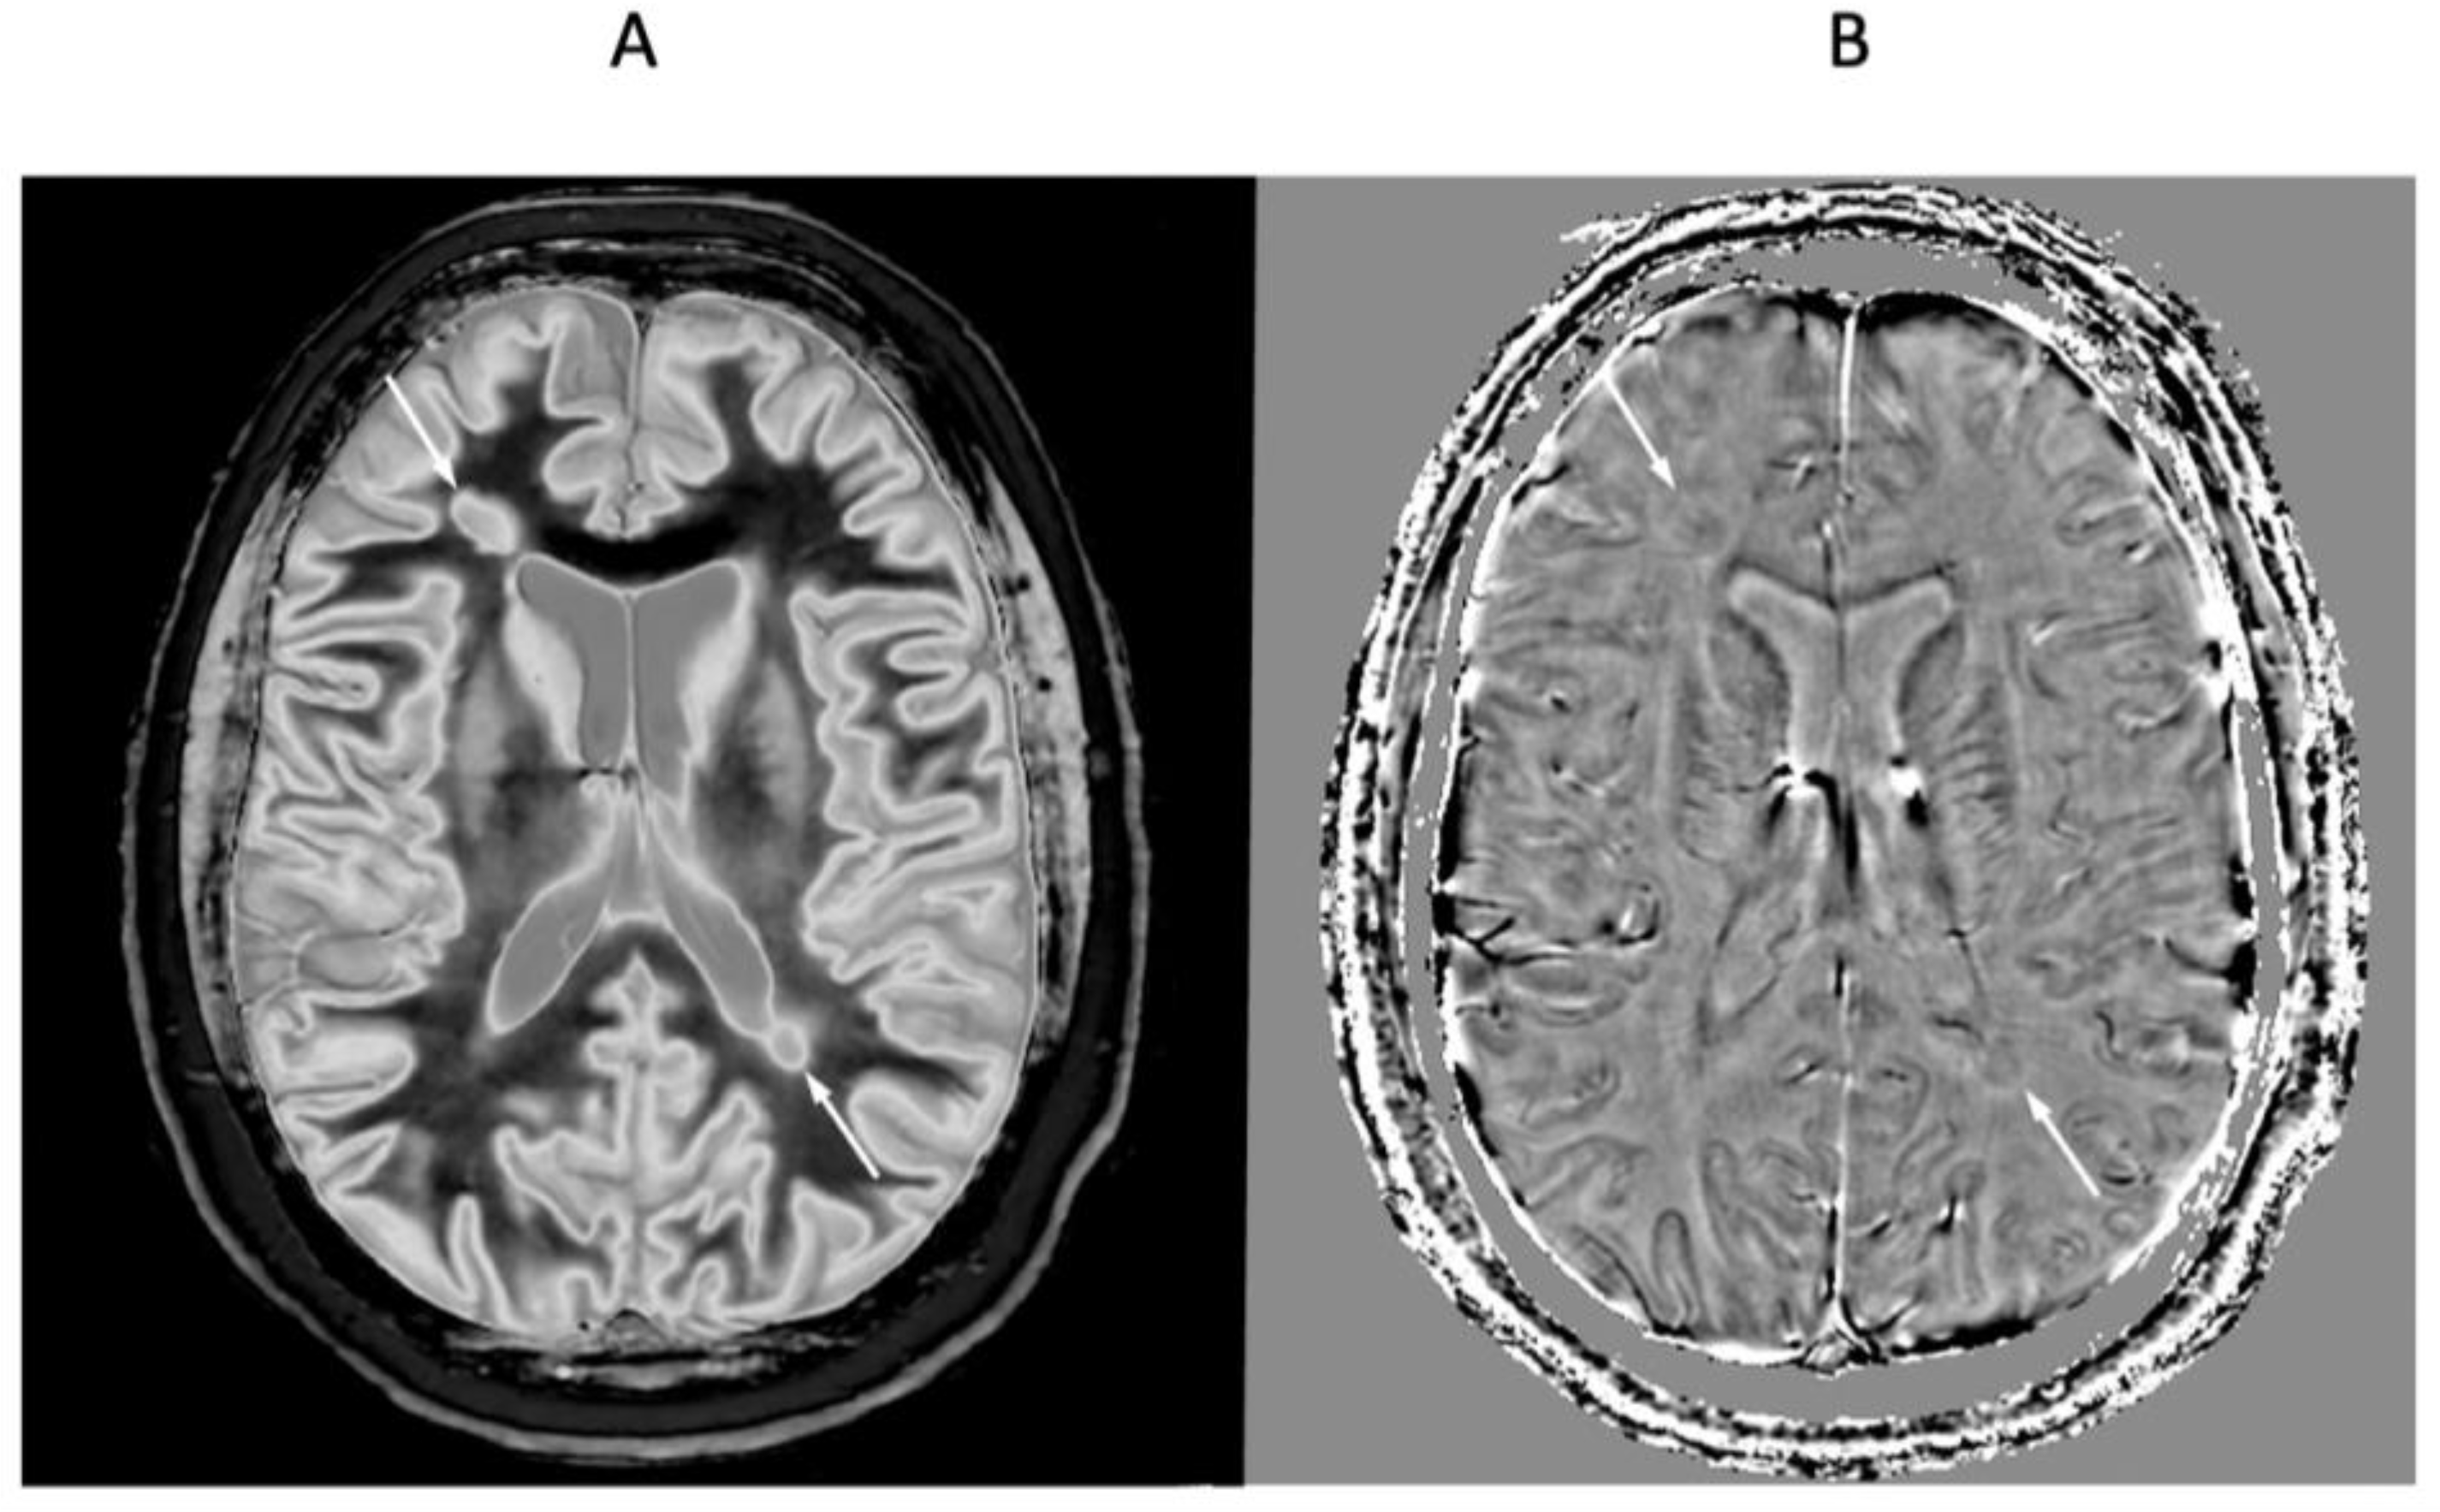

2.4. Log then Subtracted Inversion Recovery (lSIR) Sequences

2.5. Composite (c) Bipolar Filters (T1 as well as T2, T2*, and/or D*)